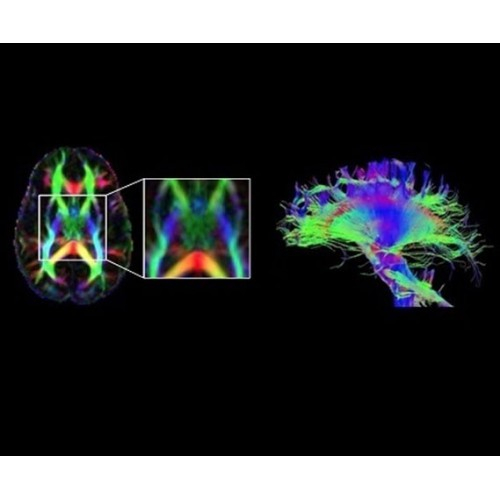

• Специальный пакет приложений для измерения и сравнения объемных изображений ЦНС с нормами поможет вам в диагностике нейродегенеративных заболеваний, а дополнительные инструменты визуализации — в постановке точного диагноза с помощью бета-амилоидов и радиоизотопных маркеров ФДГ.

В системе SIGNA PET/MR есть все инструменты, необходимые для выявления маркеров разных заболеваний и для создания новых протоколов. ПЭТ/МРТ можно использовать совместно с мультиядерной спектроскопией в лаборатории in vivo для изучения быстрых биохимических процессов. Кроме того, PET ToolBox и набор инструментов Orchestra предоставляют персональный доступ к функциям реконструкции изображений для ПЭТ и МРТ, ускоряя и упрощая работу с необработанными данными.